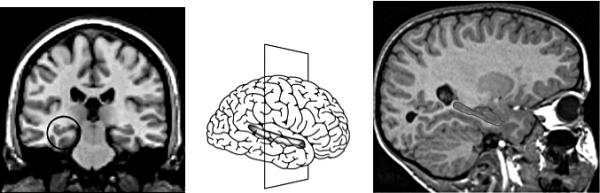

Хотя гиппокамп — сравнительно небольшая часть головного мозга, он очень важен для всей его работы (см. рис. 1.8). Гиппокамп запоминает не только происходящие с нами конкретные события, но и места («адреса») в коре больших полушарий головного мозга, где в закодированном виде хранятся все детали каждого события и связанные с ними свойства и признаки. Именно благодаря гиппокампу мы можем собрать эти детали воедино и подробно рассказать о случившемся: «Вчера в половине третьего я на кухне уронил на пол зеленую чашку, и она разбилась на тысячу осколков». В отличие от коры больших полушарий головного мозга, которая в результате длительного обучения создает в своих многочисленных модулях упорядоченные карты различных свойств и признаков, гиппокамп постоянно занимается тем, что связывает друг с другом поступающие к нему импульсы из активизированных участков в коре больших полушарий головного мозга и таким образом формирует нашу долговременную память о событиях нашей жизни и связанных с ними переживаниях.

1.8. Моя маленькая дочь Анна приходит ко мне после того, как ее искупали. Она улыбается мне, она теплая, пахнет ванильной пеной для ванны и говорит: «Привет!» Кора моего головного мозга обрабатывает впечатления, активизируя соответствующие участки (верхний левый рисунок). Сопутствующие положительные эмоции одновременно активизируют гиппокамп; клетки гиппокампа запоминают взаимосвязи активизации благодаря тому, что они очень быстро выстраивают между собой соответствующие аналогичные связи (верхний правый рисунок). После этого они могут в свою очередь активизировать ответные участки в коре головного мозга и тем самым повторно воспроизвести мое первоначальное переживание (нижний левый рисунок); и когда между участками коры головного мозга, в которых закодированы признаки «теплый», «ванильный», «улыбка» и «приветствие», будет установлено надежное соединение, а целостное воспоминание отложится в коре, гиппокамп наконец-то позволит себе его забыть (нижний правый рисунок).